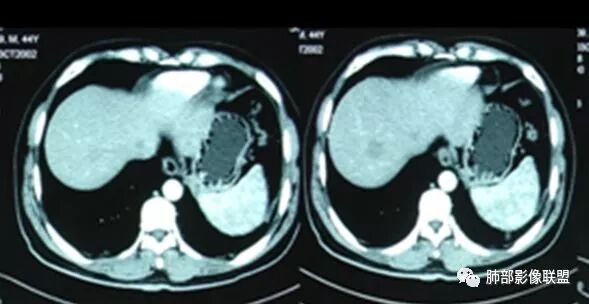

腹增强CT

若尘:腹部动脉增强不像脓肿没意见:肝功异常了,小心张立:增强后表现很明显,很好区别。初学者:我说实话那个腹部给的增强图片对比度调的不好不太像囊肿低密度和边缘不是非常清楚。但是图片给的不好,不是非常能肯定。wonderful:增强的话 脓肿壁会强化 这是鉴别点?初学者:对,但是有时候不会典型

脾大,肝内结节中央似有点状血管通过,炎性可能

但不是典型的脓肿南边:综合临床,影像,肺部是血道来源感染,肺克雷伯杆菌肺炎放前面。毛霉菌待排吧没意见:低蛋白、ALT异常可能间接提示肝脏问题go and see:这个肝脓肿确实不够典型多少。初学者:

4.本例肝脏的病灶并未出现典型肝脓肿图像特征,病灶密度及中央血管样结构显然不符合一般的囊肿。应当说,它是感染灶,但并未液化形成脓腔。